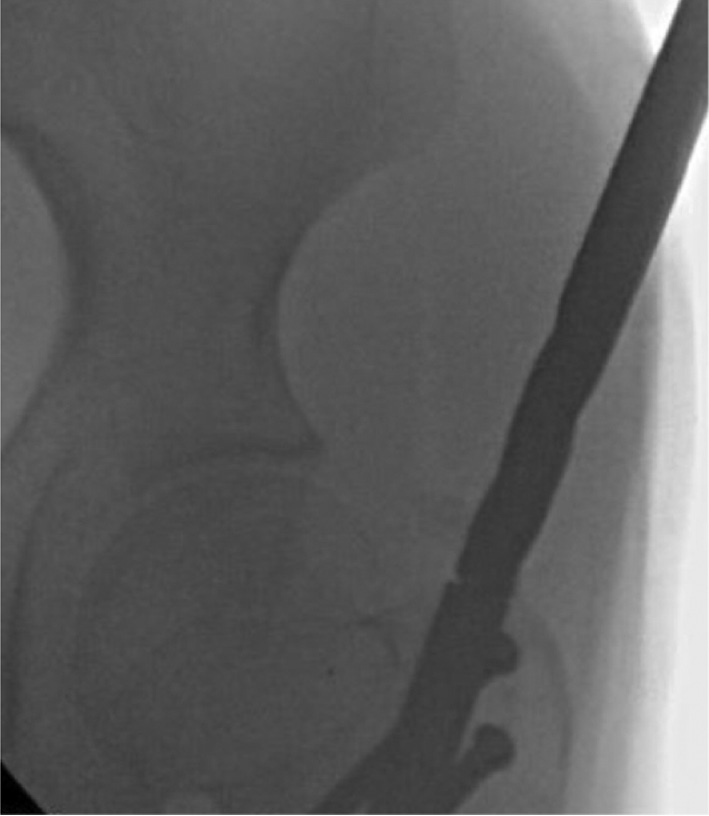

Figure 24. It is important that the guidewire is aligned perfectly to the center of the nail under fluoroscopy in both the coronal and sagittal planes.

jposna20220031_fig24.jpg